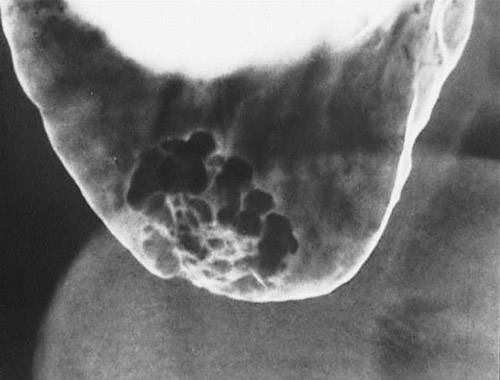

This barium enema demonstrates a villous adenoma of the colon. Note that this mass is sessile and that contrast extends between the long fronds of the adenoma that project into the colonic lumen (unlike a solid carcinoma).